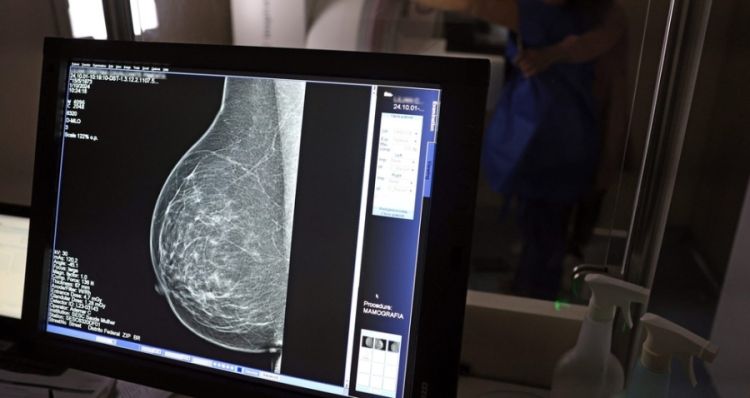

Os pesquisadores utilizaram IA para analisar a quantidade de depósitos de cálcio nas artérias do tecido mamário. A quantidade de calcificação foi classificada como grande, moderada, leve ou ausente.

A categorização foi comparada posteriormente com o desenvolvimento de doenças cardiovasculares graves, como AVC e infarto, e com dados de morte por doença cardiovascular.

Os resultados apontaram diferentes níveis de risco, a depender do estágio de calcificação:

- Mulheres com calcificação leve - 30% mais probabilidade de sofrer um evento cardiovascular grave.

- Mulheres com calcificação moderada - 70% mais risco de sofrer um evento cardiovascular grave.

- Mulheres com calcificação grande - duas a três vezes mais chance de sofrer um evento cardiovascular grave.

"Descobrimos que quanto mais cálcio visível nas artérias da mama em uma mamografia, maior o risco de a mulher sofrer um evento cardíaco grave, como infarto, AVC ou insuficiência cardíaca", explica Trivedi.